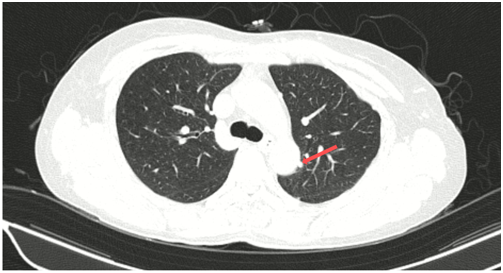

Ct ngực sau điều trị:

Theo dõi định kỳ bằng lâm sàng, chụp CT ngực và MRI sọ não sau 3 tháng, 6 tháng và 15 tháng cho thấy:

- Tổn thương phổi và não giảm kích thước rõ rệt.